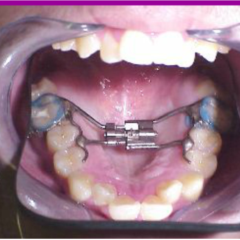

Topic: Expansion

• We are discussing expansion. I am sure, we all have done few. We will revisit protocol.

• There are also other types of expanders besides RPE and we will look intot hem as well.

• Narrow maxilla is indicative of expansion in presense of a crossbite however, expansion is being used as a corrective treatment in Class II and Class III cases as well. We will examine latest literature on the subject.